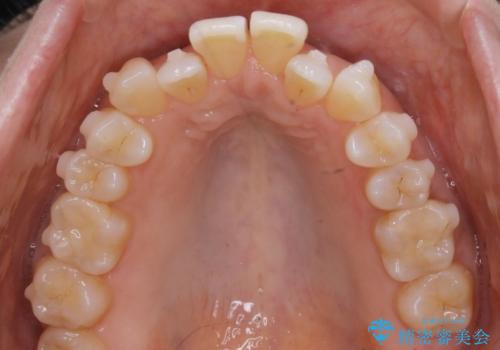

拡大とIPR

歯列の幅を拡大することにより作れるスペースは想像より大きく、実際に拡大だけでガタつきが治せるというケースもあります。

その他の歯のガタつきをとるためのスペース作りの方法の一つにディスキング(IPR)という方法があります。

歯と歯の間を一ケ所あたり最大0.5mmまでの範囲内で削ることで歯自体が少し小さくなり、それにより作られるスペースを数ヶ所分合わせることで合計で数mmの大きなスペースが作れるという方法です。

当院ではなるべく歯の機能や見た目に影響の出ないよう、作業時に拡大鏡の使用や削るタイミングの微調整を行っています。